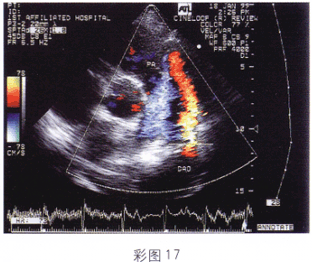

4.該病例心臟超聲檢查如圖(彩圖17)所示,最可能的診斷是

A.主動脈-肺動脈間隔缺損

B.動脈導管未閉

C.肺動脈瓣狹窄

D.肺動脈瓣反流

E.右心室流出道狹窄

正確答案:B解題思路:降主動脈與左肺動脈間見分流信號。